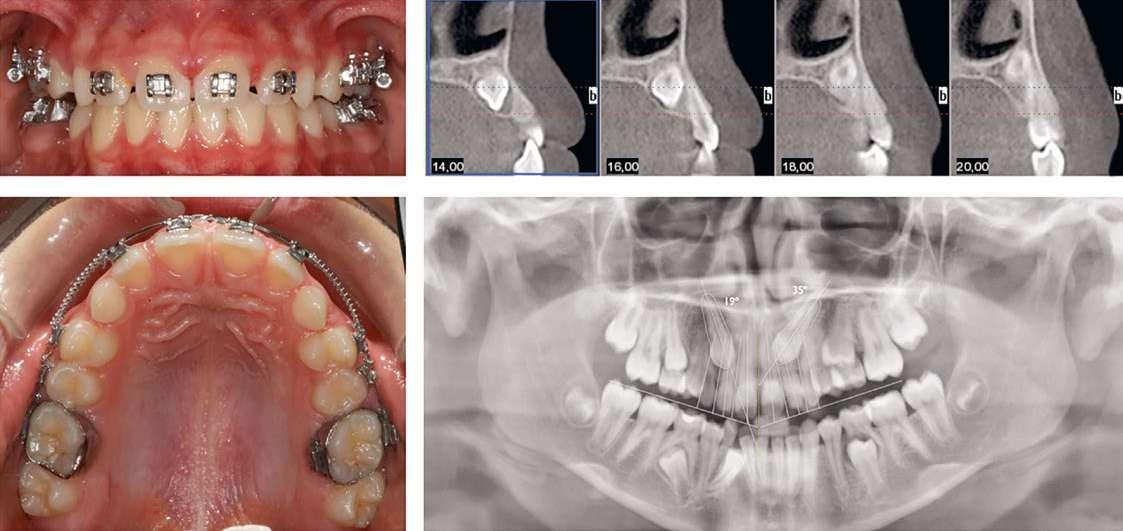

Se presentan fotografías clínicas de la evolución y seguimiento a 6 meses, 12 meses y a 5 años (Figs. 8-10). A pesar de una mínima recidiva de menos de 1 mm en la recesión del diente 2.1, es interesante y reconfortante observar la gran estabilidad clínica de los tejidos blandos, así como un color, textura y forma muy armónicos de toda la encía tratada. En gran parte también gracias a un excelente cepillado y mantenimiento periodontal.

los 6 meses post-operatorio, antes del

10. Seguimiento a 5 años post-operatorio. Obsérvese el buen color, textura y forma gingival, así como la estabilidad de los tejidos blandos aumentados gracias a la excelente higiene oral del paciente y el correcto mantenimiento periodontal.

Figura 8. Seguimiento a

blanqueamiento dental.

Figura

Figura 9. Seguimiento a 12 meses post-operatorio, una vez realizado el blanqueamiento dental domiciliario.

Finalmente, 6 meses después de la cirugía y una vez confirmada la estabilidad de los tejidos blandos, se realizó blanqueamiento domiciliario.

Seguimiento y evolución del caso